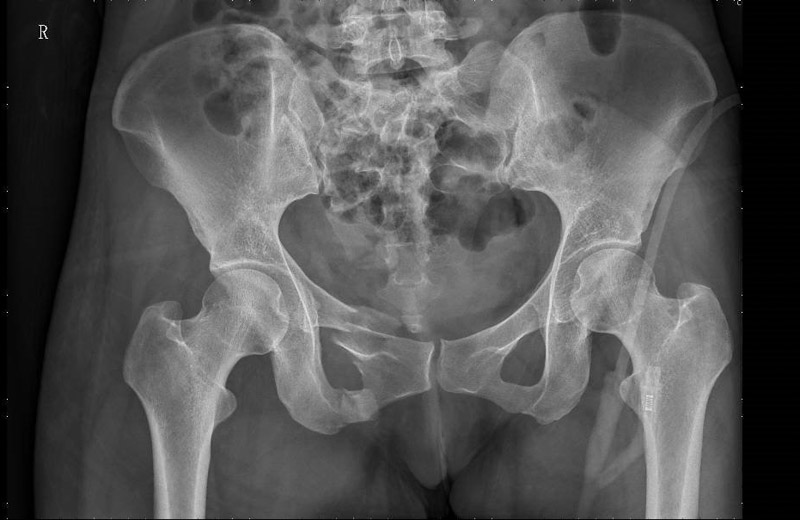

患者周女士在走路時(shí)不慎被車撞傷,被120送至當(dāng)?shù)蒯t(yī)院,清醒后感覺臀部劇痛難忍,雙髖活動(dòng)受限,為求進(jìn)一步治療,轉(zhuǎn)入了柳州市人民醫(yī)院創(chuàng)傷骨科,經(jīng)CT檢查,患者為骨盆骨折,需手術(shù)治療。

骨盆位置深,內(nèi)部臟器結(jié)構(gòu)豐富,血管神經(jīng)復(fù)雜,一旦發(fā)生損傷,常常導(dǎo)致相應(yīng)的血管神經(jīng)損傷和大出血,所以骨盆骨折手術(shù)一直被認(rèn)為是創(chuàng)傷骨科中最復(fù)雜的手術(shù)之一。且傳統(tǒng)切開復(fù)位內(nèi)固定手術(shù)對(duì)患者傷害較大,容易造成術(shù)中血管神經(jīng)的損傷、術(shù)后感染等并發(fā)癥的發(fā)生。